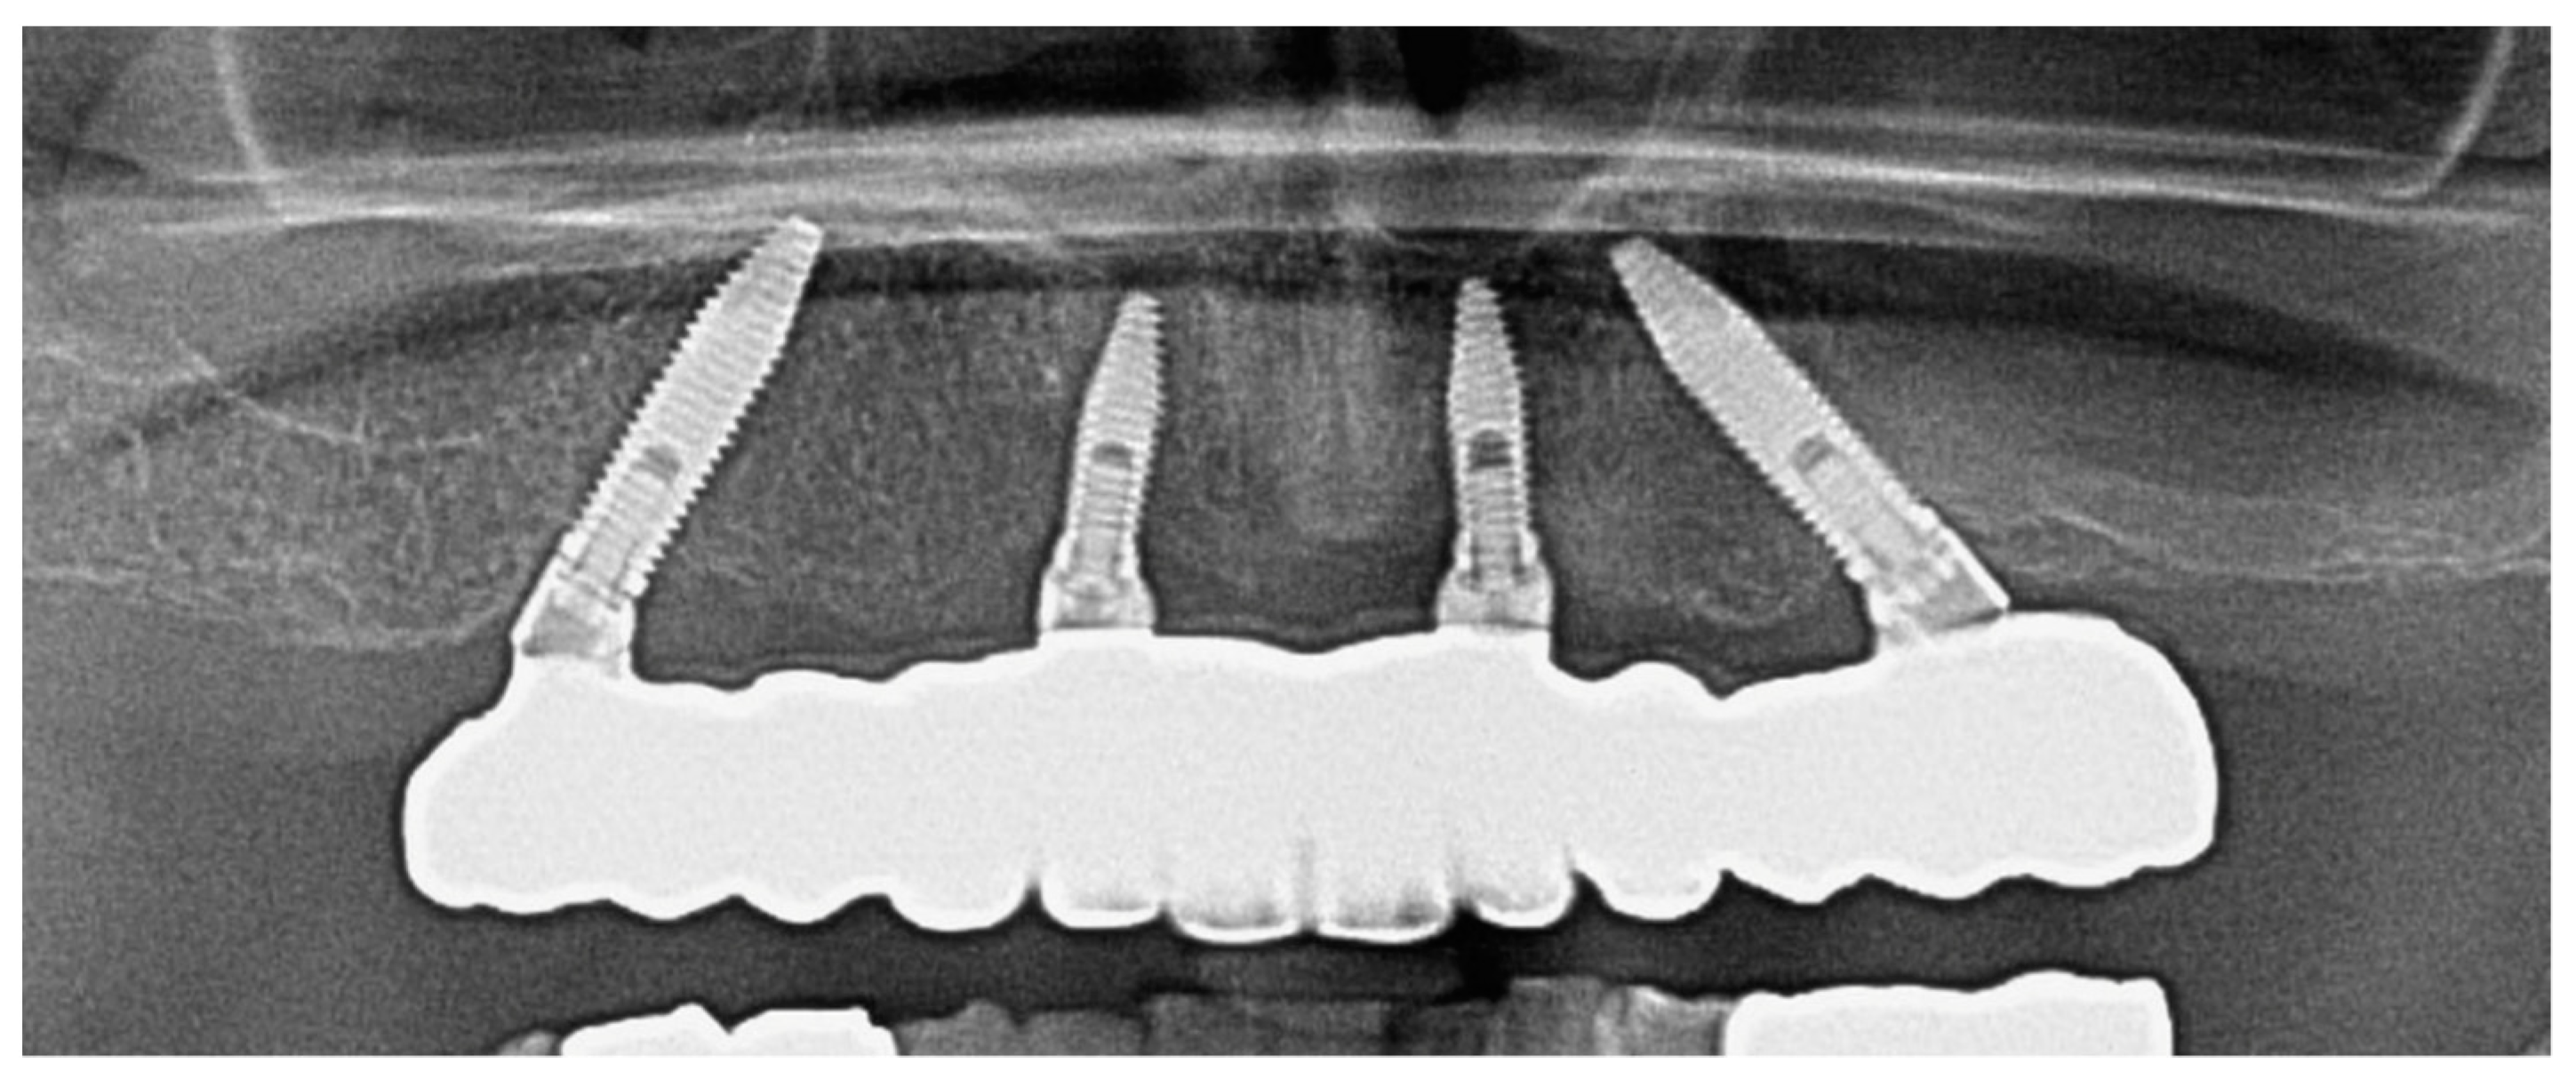

1. Introduction

3.2. Marginal Bone Level